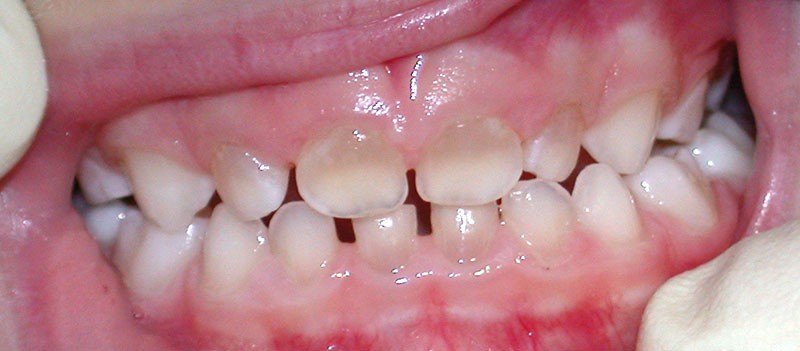

Teinte opalescente grise à jaune ambrée, couronnes globuleuses, calcifications intra-pulpaires, racines fines et courtes, attrition précoce, nécrose aseptique… Ces anomalies cliniques et radiographiques décrivent le tableau de la dentinogenèse imparfaite (DI) isolée de type 2. Cette anomalie génétique à transmission autosomique dominante est liée à un défaut de DSPP, gène de la sialophosphoprotéine dentinaire [1, 2]. Des anomalies dentinaires similaires résultent également de mutations de ce gène. Les avancées en recherche génétique tendent à réunir ces pathologies sous une même étiologie.

Un diagnostic précoce est primordial, car il existe aussi une forme associée à une anomalie osseuse, l’ostéogenèse imparfaite. Le chirurgien-dentiste est donc au premier plan pour dépister ces anomalies et limiter dès le plus jeune âge leurs conséquences infectieuses, fonctionnelles et esthétiques.